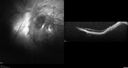

Traumatic Peripapillary Subretinal Hemorrhage1 views16 year old hit in eye with finger during basketball. Vision is 20/25 and there is a peripapillary hemorrhage.Apr 13, 2026